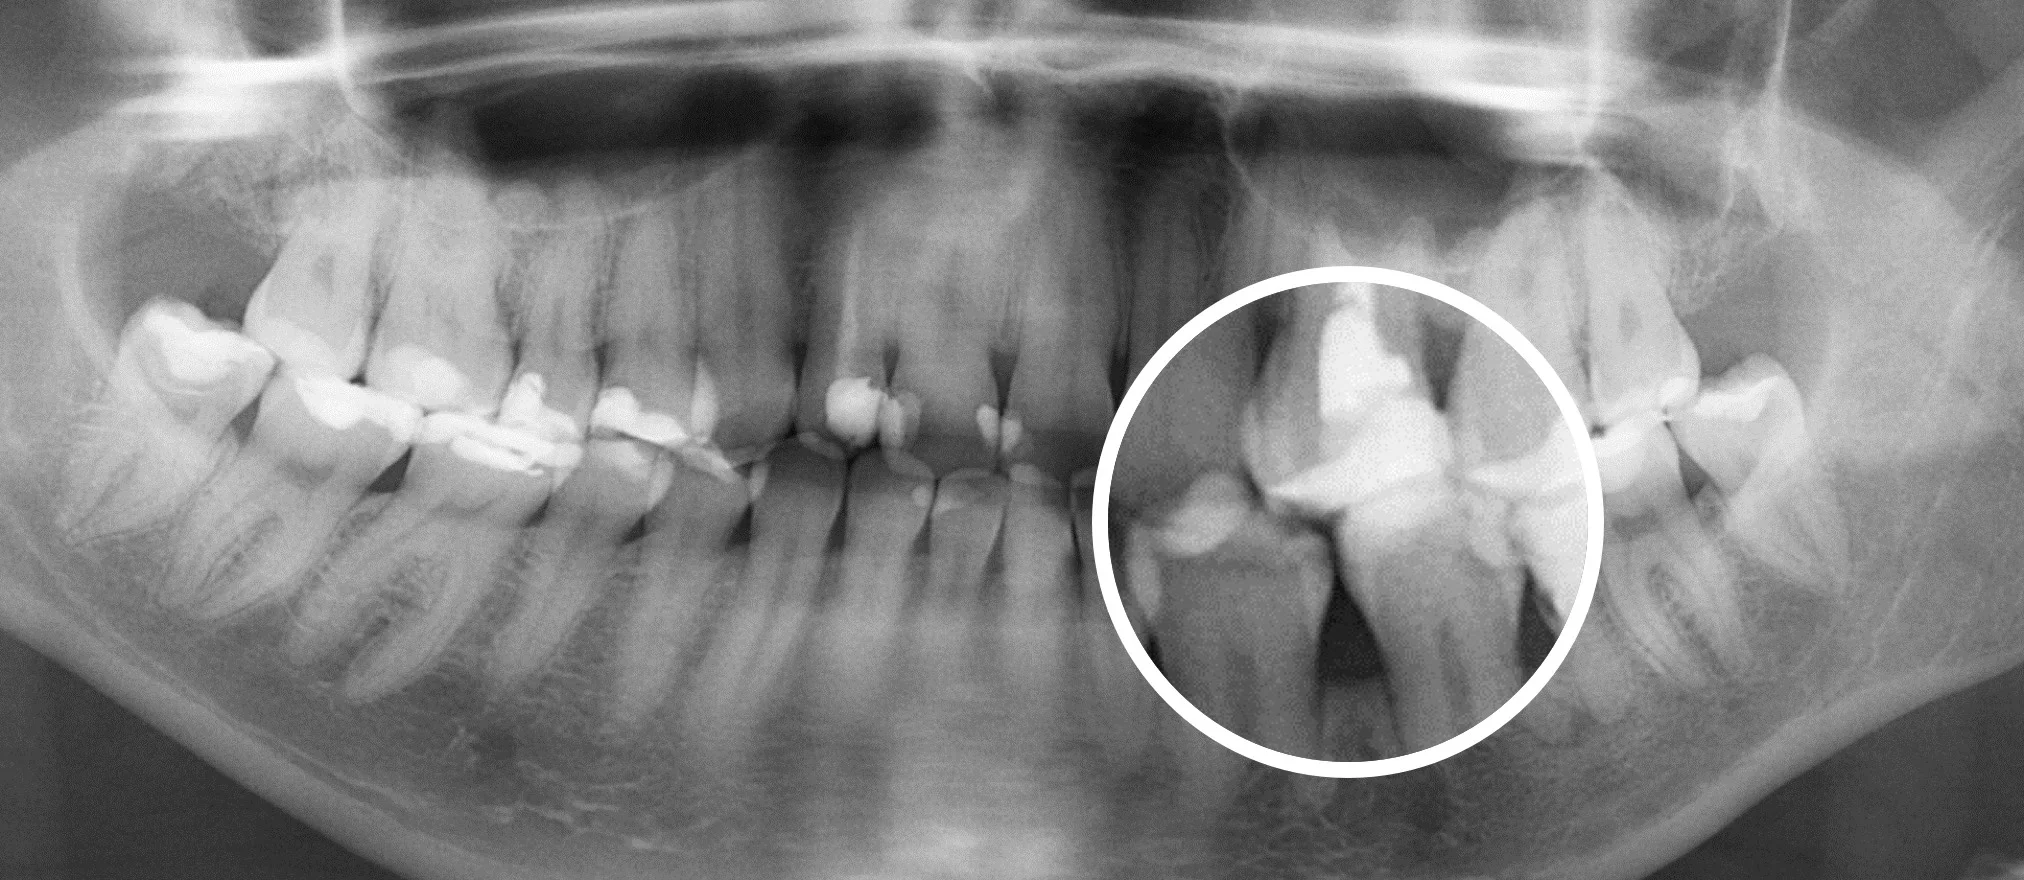

Еще 10 лет назад для того, чтобы провести диагностику зубов стоматологи использовали прицельные R-снимки и ОПГ снимки. Это снимки, которые делаются в 2D формате. Единственное, что врач мог делать с данным снимком, это приближать и удалять изображение.

На смену 2D снимкам пришли КТ снимки (компьютерная томография], которые в обиходе называют 3D снимками —новый уровень диагностики.

3D снимки позволяют стоматологам рассмотреть зубы под разными углами.

Врач изучает 3D снимки на компьютере и в отличии от 2D снимков, он может крутить изображение под любым углом, который ему необходим, заглядывать «внутрь» каждого зуба.

Сравнение 2D и 3D снимков